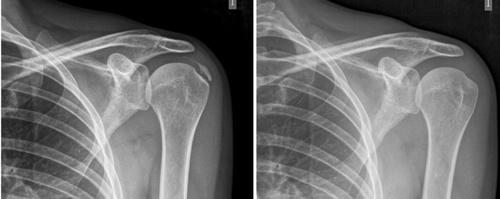

Figura 1

Figura 2

Figura 3

Figura 4

Figura 5

Figura 6